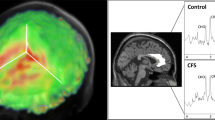

Data analysis

MRS data were analyzed using the Project Review and Analysis (PRANA) and Map Integrated Spectrum (MINT) modules within MIDAS. Voxels were excluded based on the following criteria: (i) fitted metabolite linewidth above 13 Hz; (ii) outlying values 2.5 standard deviations above or below the mean of all valid values within the image; (iii) a Cramér-Rao Lower Bound (CRLB) for creatine (CR) fitting above 40%; and (iv) greater than 30% contribution from cerebrospinal fluid to the voxel volume. Atlas-defined ROIs were inversely transformed into subject space, and spectral averaging was performed over the ROIs to obtain CHO, MI, NAA, LAC, and CR values (area under curve, AUC) in each region. Representative integrated spectra in the right frontal and parietal cortices for one participant from the RA and control group are shown in Fig. 1. Metabolites were expressed as ratios relative to CR to allow for comparisons with other studies. Brain temperature was calculated based on the metabolite maps using the following formula: T = − 102.61 × Δ(ƒH2O-ƒCR) + 206.1 °C where ƒH2O and ƒCR represent the resonant frequencies of the water and CR peaks, respectively [24].

Main results

There were no significant MRSI outcome differences between groups for any brain region at the p < 0.0023 threshold. Maps of the average CHO/CR ratios in the RA and control group are visualized in Fig. 2. Results for all group contrasts can be found in Online Resource 2.

We previously reported elevated CHO, LAC, MI, and temperature throughout the brain in myalgic encephalomyelitis/chronic fatigue syndrome (ME/CFS) [14]. Despite the fact that both the ME/CFS group in the previous study and RA group in the current study had significant self-reported fatigue (≥ 6 out of 10), only the ME/CFS group evidenced signs of brain inflammation. The difference in results could indicate ME/CFS is a CNS disease, while RA is a disease primarily of the peripheral joints. The MRSI scan may, therefore, be useful in identifying individuals with central inflammatory origins of fatigue.